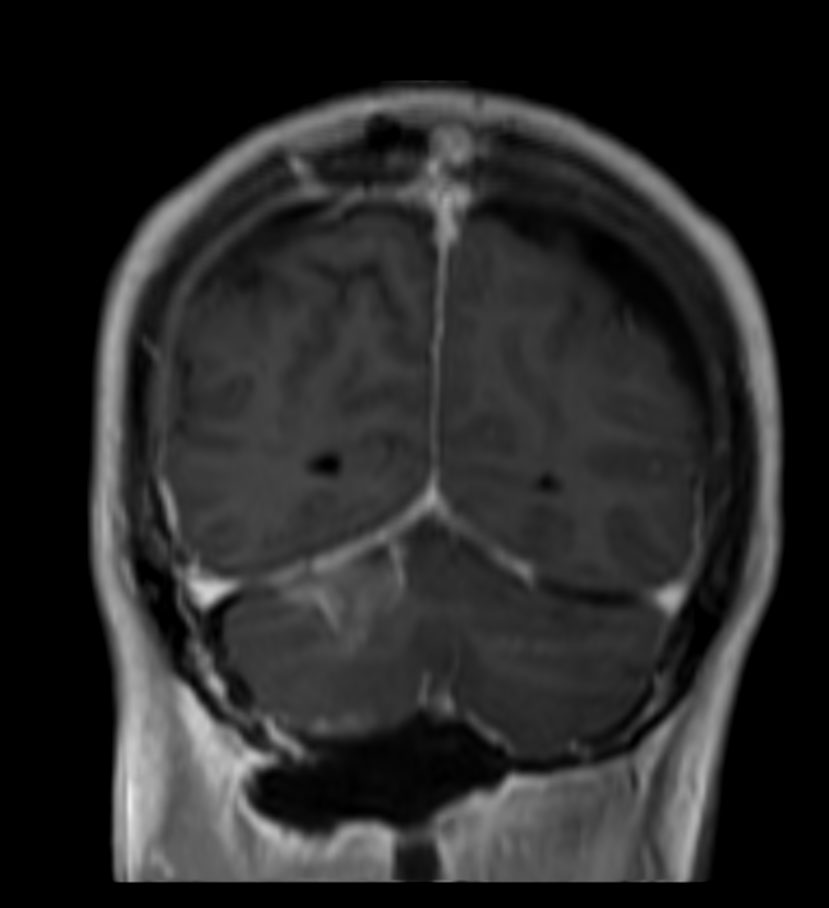

3D T1W FFE post contrast (coronal reformat)